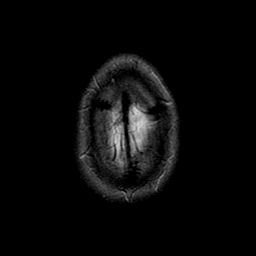

glioma overlay -- Slice #26

[Home][Help][Clinical] Slice 26